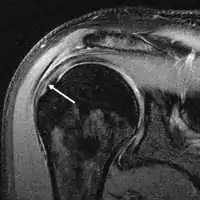

MRI

MRI of normal shoulder intratendinous signal

MRI of rotator cuff full-thickness tear

Magnetic resonance imaging (MRI) and ultrasound[46] are comparable in efficacy and helpful in diagnosis, although both have a false positive rate of 15–20%.[47] MRI can reliably detect most full-thickness tears, although very small pinpoint tears may be missed. In such situations, an MRI combined with an injection of contrast material, an MR-arthrogram, may help to confirm the diagnosis. It should be realized that a normal MRI cannot fully rule out a small tear (a false negative) while partial-thickness tears are not as reliably detected.[48] While MRI is sensitive in identifying tendon degeneration (tendinopathy), it may not reliably distinguish between a degenerative tendon and a partially torn tendon. Again, magnetic resonance arthrography can improve the differentiation.[48] An overall sensitivity of 91% (9% false negative rate) has been reported, indicating that magnetic resonance arthrography is reliable in the detection of partial-thickness rotator cuff tears.[48] However, its routine use is not advised, since it involves entering the joint with a needle, with the potential risk of infection. Consequently, the test is reserved for cases in which the diagnosis remains unclear.